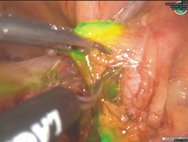

前哨淋巴結,就是指與腫瘤連接的第一個淋巴結。因術中只摘除有顯影的前哨淋巴結(圖二),因此大大減少了術後的後遺症如手臂麻痺、疼痛、淋巴水腫等,改善了患者的生活品質。這項技術近年來也開始被應用在婦癌手術如外陰癌、子宮頸癌及子宮內膜癌之手術。本院婦癌團隊自2017年中開始推行前哨淋巴結造影,至今已執行超過70例,並在2020年分析了過去兩年半共34例接受前哨淋巴結造影的子宮內膜癌患者的治療結果,發現前哨淋巴造影並不會增加癌症復發比率或死亡率,反而可以減少手術流血量且摘除之淋巴結數量也較少。

圖二、前哨淋巴造影 (綠色螢光為顯影的淋巴結)